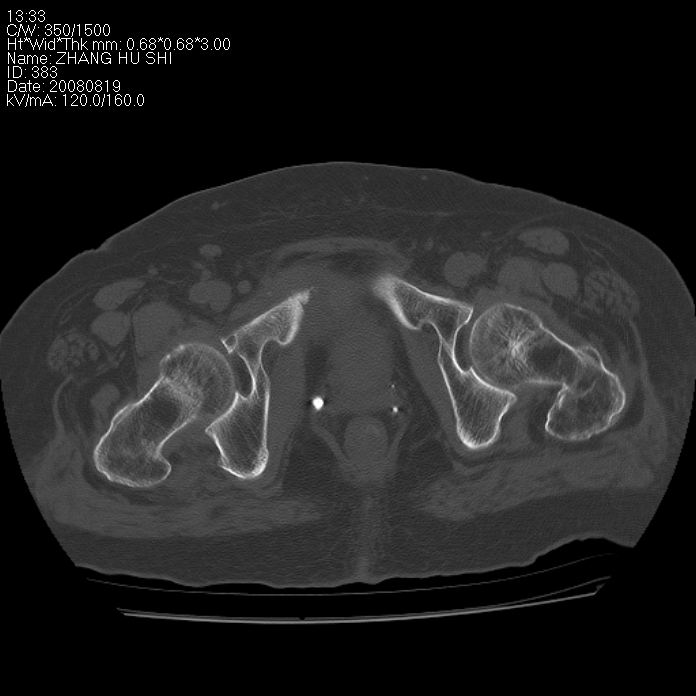

标题: CT15287:女 93岁 右髋关节疼痛 原左侧粗隆间骨折 CT发现右耻 [打印本页]

标题: CT15287:女 93岁 右髋关节疼痛 原左侧粗隆间骨折 CT发现右耻

支持转移并周围软组织侵犯右闭孔内肌侵犯,但tb不能完全除外。

耻骨软骨肉瘤可能性大